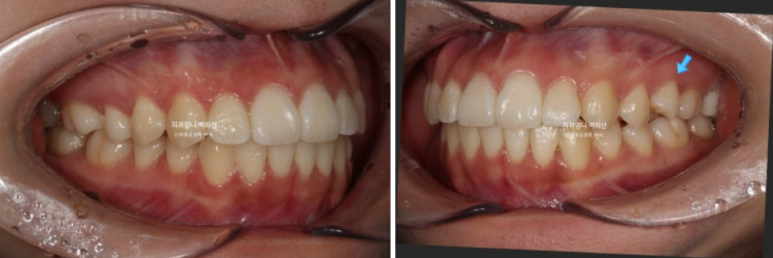

2023년 12월 앞니 부분교정을 원해서 내원한 분 입니다.

앞니 두 개가 크기도 하고 내려와 있습니다.

파란 화살표에 작은어금니 덧니도 보입니다.

아래 앞니가 많이 삐뚤 합니다.

어금니 교합이 그리 좋은 편은 아니었지만 환자분은 씹는데 불편함을 못 느끼는 상태였고 앞니 배열만 원하셨습니다.